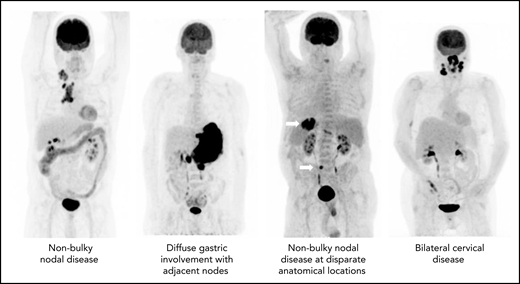

The precise definition of LS-DLBCL is not standardized. Although it is clear that localized disease is restricted to Ann Arbor stages I to II, variation among studies exists in definition of bulk (maximum dimension ranging between 5 and 10 cm), inclusion of B symptoms, and staging methodology. Although not always explicitly stated, LS-DLBCL generally implies disease that can be readily encompassed within a reasonable RT field, as historically RT was considered a mainstay of therapy (Figure 1).7-12

The diagnostic and staging work up for LS-DLBCL should follow standard DLBCL recommendations including baseline clinical and organ function assessments plus Ann Arbor staging (Table 1). Accurate identification of LS-DLBCL has significant treatment implications, particularly in patients being considered for abbreviated therapy. PET plus computed tomography (PET-CT) is recommended for all DLBCL patients due to its superiority in identifying disease over standard contrast-enhanced CT, with PET up-staging 5% to 15% of DLBCL.13,14 The value of bone marrow biopsy (BMB) has been scrutinized in the PET-era and is listed as optional in the Lugano staging recommendations.13 PET-CT detects bone marrow involvement with high sensitivity and specificity (86% and 100%, respectively) but can miss the rare presence of indolent or low-volume disease,15 with 2% to 6% of patients with PET-determined LS-DLBCL having demonstrable marrow involvement detected exclusively by BMB, thus up-staging to stage IV disease.16-18 Thus, BMB is preferred for more accurate staging, especially if abbreviated therapy is being considered.